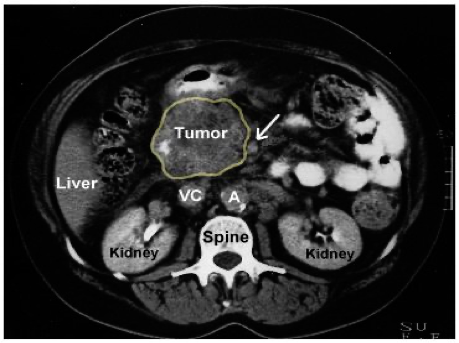

CT scan and MRI can assess the site of the tumor in the pancreas and the evidence of metastases or local invasion by the tumor (staging)

Tumor in the head of pancreas

SMA - Small bowel supply from arrow -